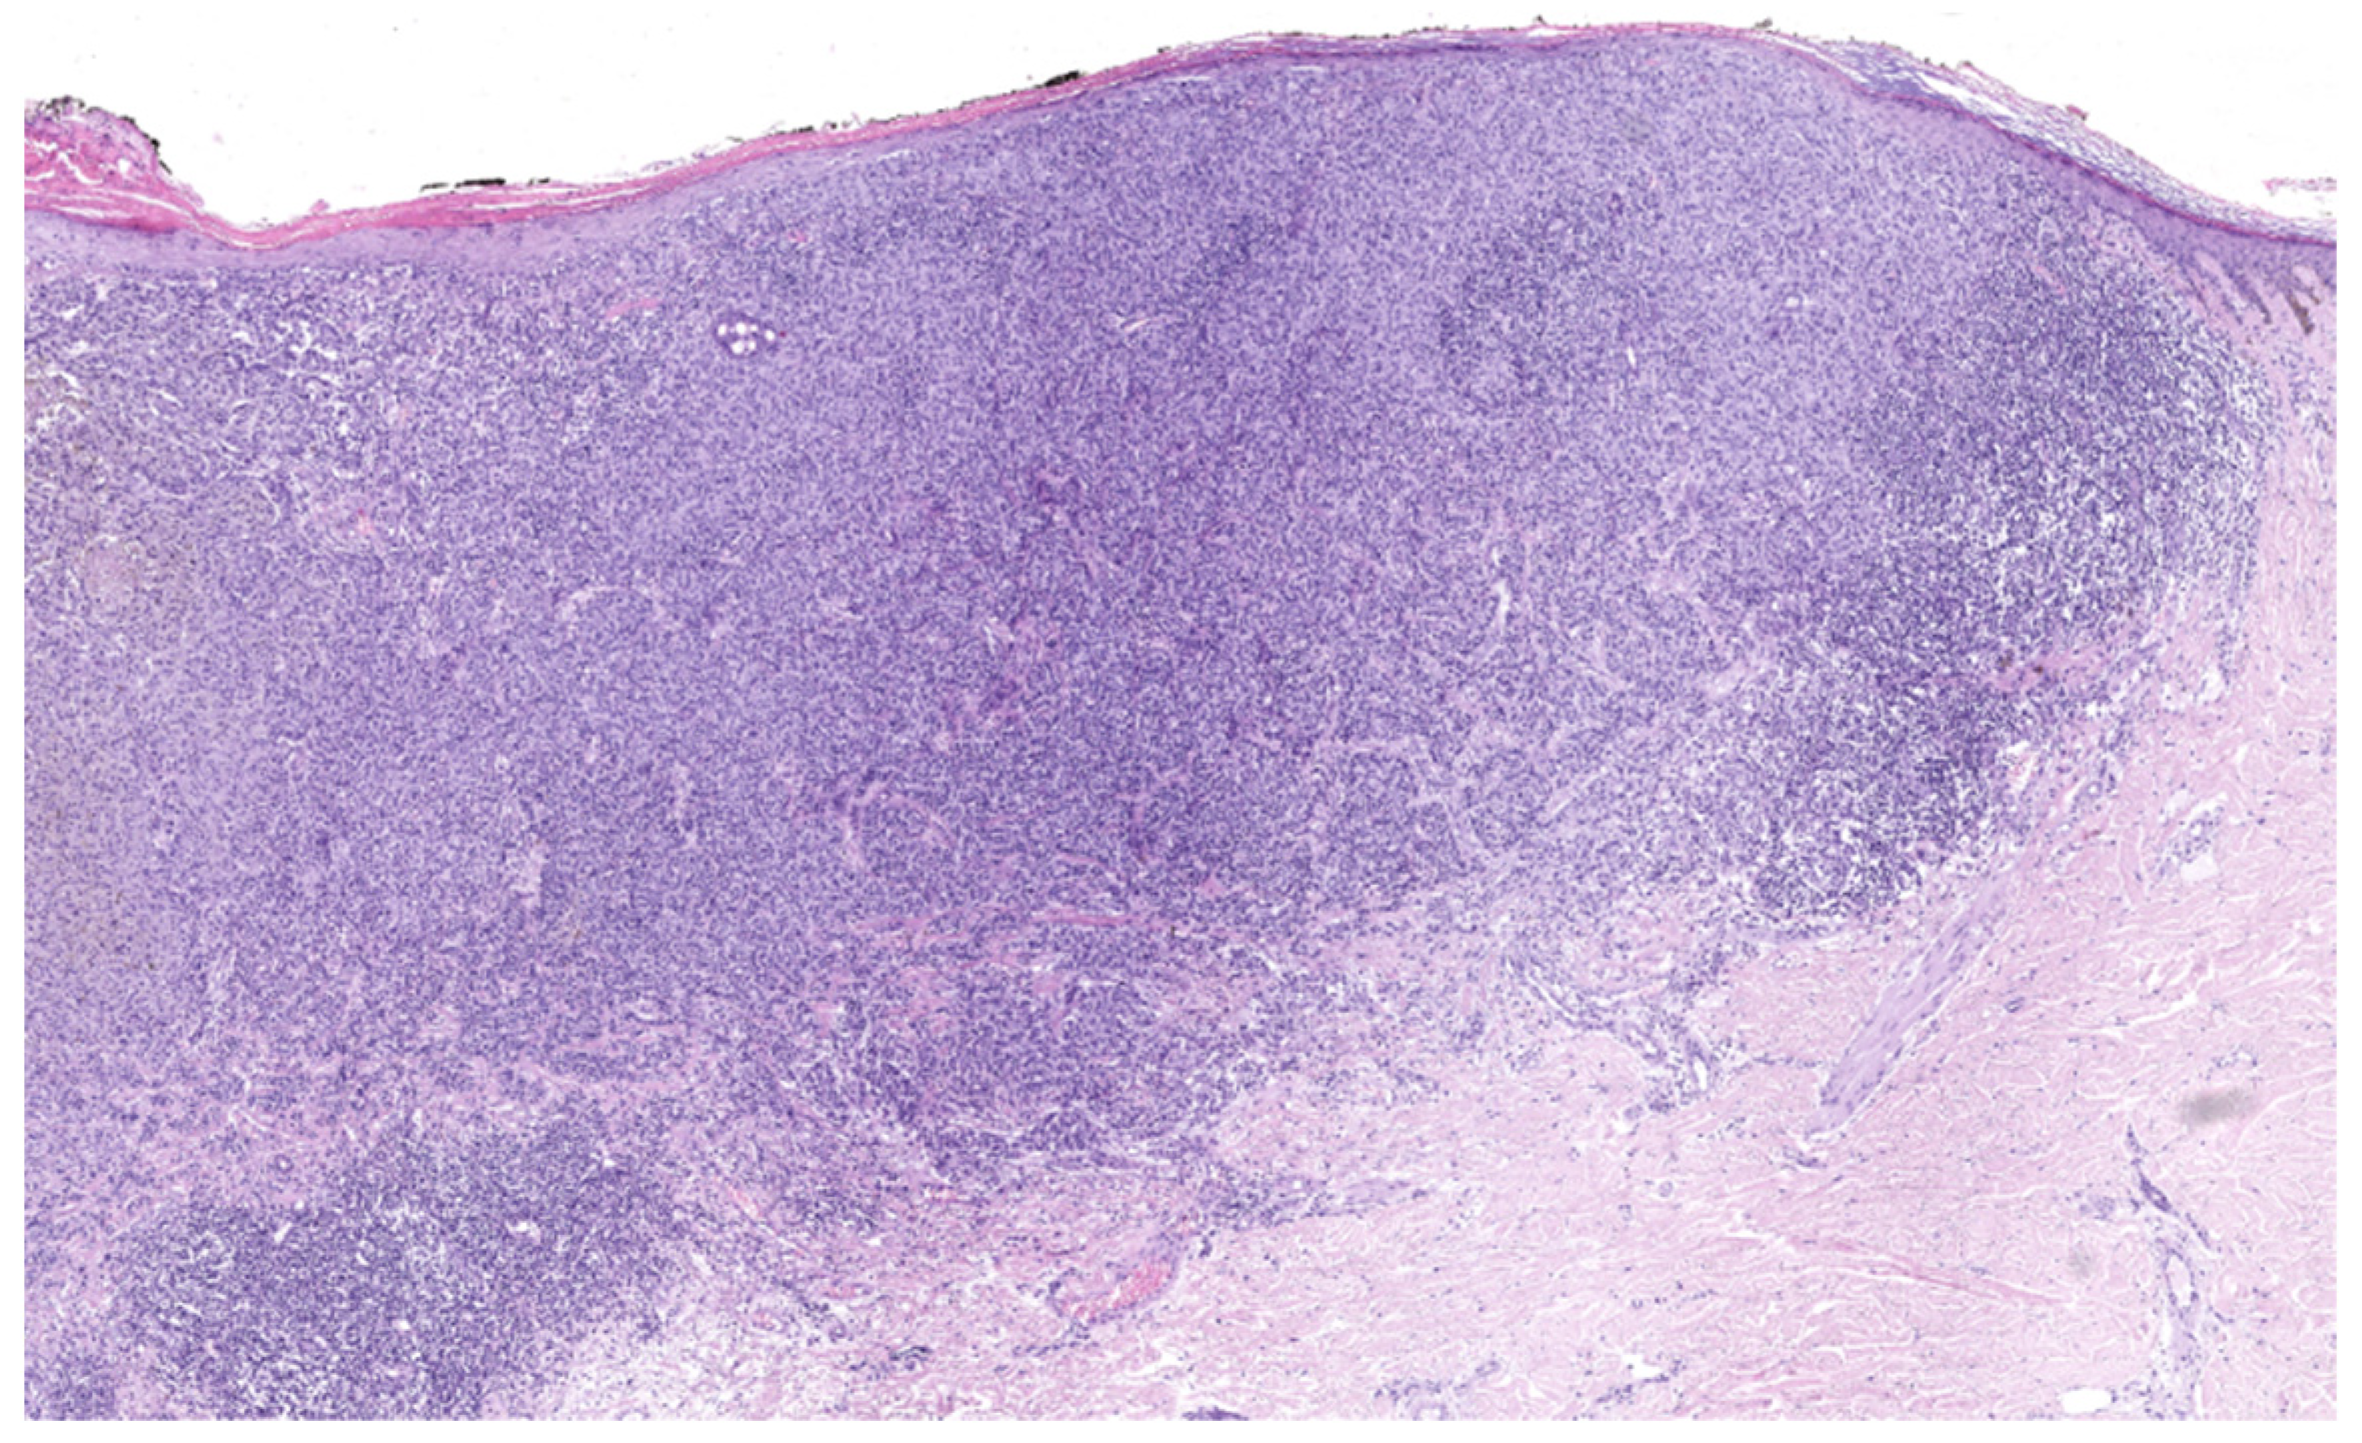

4.3. Nodular Melanoma